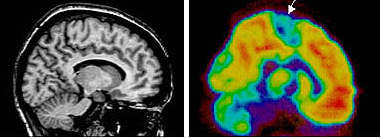

3) 뇌 기능의 이상에 대하여 PET를 이용하면 정신활동상태, 혈액의 관류상태, 포도당 대사와 산소 대사와 같은 에너지원의 대사상태, 생리적 활성 물질의 섭취 정도 등을 3차원적으로 관찰 할 수 있다. 뇌 기능 평가에 뇌혈액량, 뇌 혈류량, 뇌 산소 섭취율, 뇌 산소 소비량, 포도당 (glucose) 대사율을 참고할 수 있다.

*CT와 PET의 차이 : CT 검사는 종양 등 질환의 형태적 영상,PET 검사는 기능적 영상

공복 상태에서 PET 검사를 위해 방사선 동위원소 FDG 를 주사하면 암이 정상 조직보다 먼저 당분을 섭취하는 성질을 이용한 검사로 암의 존재 부위를 적색으로 표시 가능하다. 그러나 뇌는 포도당을 대량으로 소비하고 있기 때문에 방사선 동위원서 FDG-PET 하는 방법으로 뇌종양을 진단하기 어려운 경우가 있다. 정상적인 뇌세포는 아미노산 대사가 거의 없기 때문에 아미노산을 섭취하는 Methionine PET를 시행하고 있다.